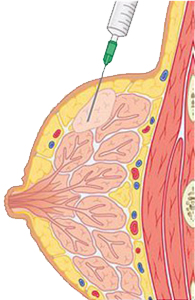

ε) Για να πραγματοποιήσουμε επεμβατική πράξη, όπου καθοδηγούμε τη βελόνα με τους υπερήχους για βιοψία συμπαγούς μορφώματος (εικόνα 4) ή εκκένωση κύστης (εικόνες 5,6) ή τοποθέτηση συρμάτινου οδηγού σε ογκίδιο για την ακριβή εξαίρεσή του χειρουργικά.

(Εικόνα 4)